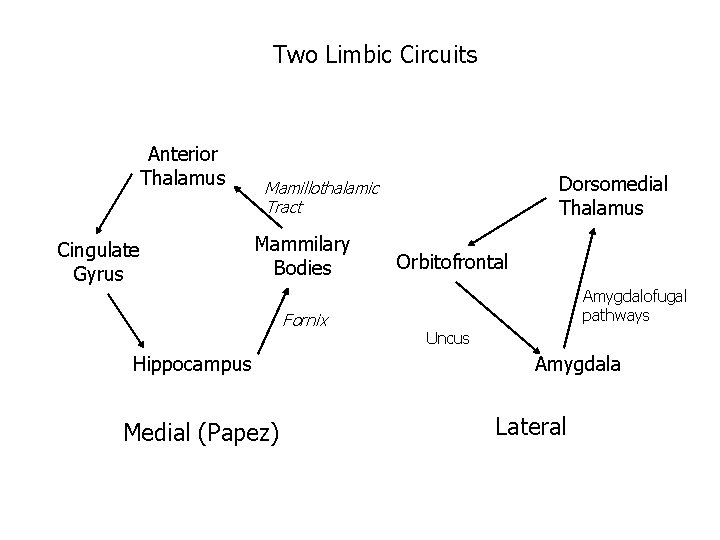

Two Limbic Circuits Anterior Thalamus Cingulate Gyrus Dorsomedial Thalamus Mamillothalamic Tract Mammilary Bodies Fornix Hippocampus Medial (Papez) Orbitofrontal Amygdalofugal pathways Uncus Amygdala Lateral

Two Limbic Circuits and the Two-system theory of amnesia Anterior Thalamus Cingulate Gyrus Dorsomedial Thalamus Mamillothalamic Tract Mammilary Bodies Orbitofrontal Amygdalofugal pathways Fornix Uncus Hippocampus Amygdala PRPH Medial (Papez) Lateral

Two Limbic Circuits and the Two-system theory of amnesia Anterior Thalamus Cingulate Gyrus Dorsomedial Thalamus Mamillothalamic Tract Mammilary Bodies Fornix Hippocampus Medial (Papez) Orbitofrontal Amygdalofugal pathways Uncus Amygdala Lateral

Two Limbic Circuits Anterior Thalamus Cingulate Gyrus Dorsomedial Thalamus Mamillothalamic Tract Mammilary Bodies Fornix Hippocampus Medial (Papez) Orbitofrontal Amygdalofugal pathways Uncus Amygdala Lateral

Two Limbic Circuits Anterior Thalamus Cingulate Gyrus Dorsomedial Thalamus Mamillothalamic Tract Mammilary Bodies Fornix Hippocampus Medial (Papez) Orbitofrontal Amygdalofugal pathways Uncus Amygdala Lateral Bauer, Grande, & Valenstein, 2003